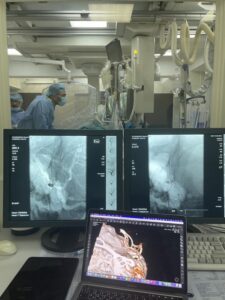

O echipă multidisciplinară de la Institutul de Medicină Urgentă, formată din neurochirurgi și chirurgi endovasculari, a salvat viața unui pacient de 27 de ani, diagnosticat cu hemoragie subarahnoidiană, cauzată de un anevrism rupt de artera comunicantă anterioară.

Anevrismul cerebral reprezintă dilatarea unui vas de sânge al creierului, ruperea căruia provoacă hemoragie, aceasta fiind o urgență medicală majoră, care în lipsa tratamentului se soldează cu consecințe tragice. Pentru tratarea anevrismului cerebral, medicii au recurs la tehnica minim invazivă de embolizare endovasculară. Aceasta presupune sigilarea anevrismului cu spirale, introduse prin arteră cu ajutorul unui tub, numit cateter. Astfel, circulația sângelui la nivelul anevrismului a fost blocată, iar pacientul este înafara pericolului. După șapte zile de la intervenție tânărul în stare bună a fost externat la domiciliu.